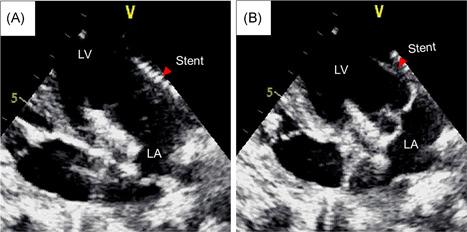

We designed a novel self-expanding mitral valve stent system consisting of an atrial flange and saddle-shaped ventricular body connected by two opposing anchors and two opposing extensions. During valve deployment, each anchor was controlled by a recurrent string. TMVI was performed in 10 pigs using the valve prosthesis through apical access to verify technical feasibility. Echocardiography and ventricular angiography were used to assess hemodynamic data and valve function. Surviving pigs were killed 4 weeks later to confirm stent deployment.

Ten animals underwent TMVI using the novel mitral valve stent. Optimal valve deployment and accurate anatomical adjustments were obtained in nine animals. Implantation failed in one case, and the animal died 1 day later due to stent mismatch. After stent implantation, the hemodynamic parameters of the other animals were stable, and valve function was normal. The mean pressure across the mitral valve and left ventricular outflow tract were 2.98 ± 0.91 mmHg and 3.42 ± 0.66 mmHg, respectively. Macroscopic evaluation confirmed the stable and secure positioning of the stents. No obvious valve displacement, embolism, or paravalvular leakage was observed 4 weeks postvalve implantation.